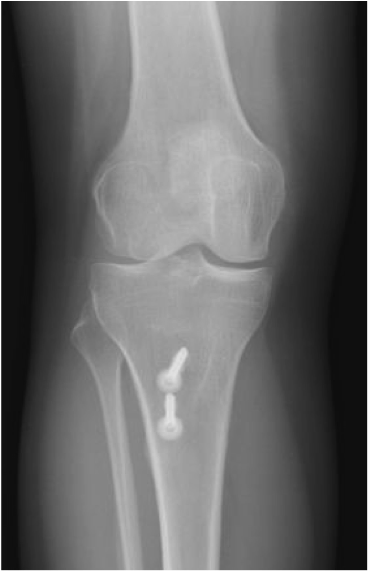

Instabilité rotulienne

Traitement chirurgical

Ligamentoplastie du MPFL